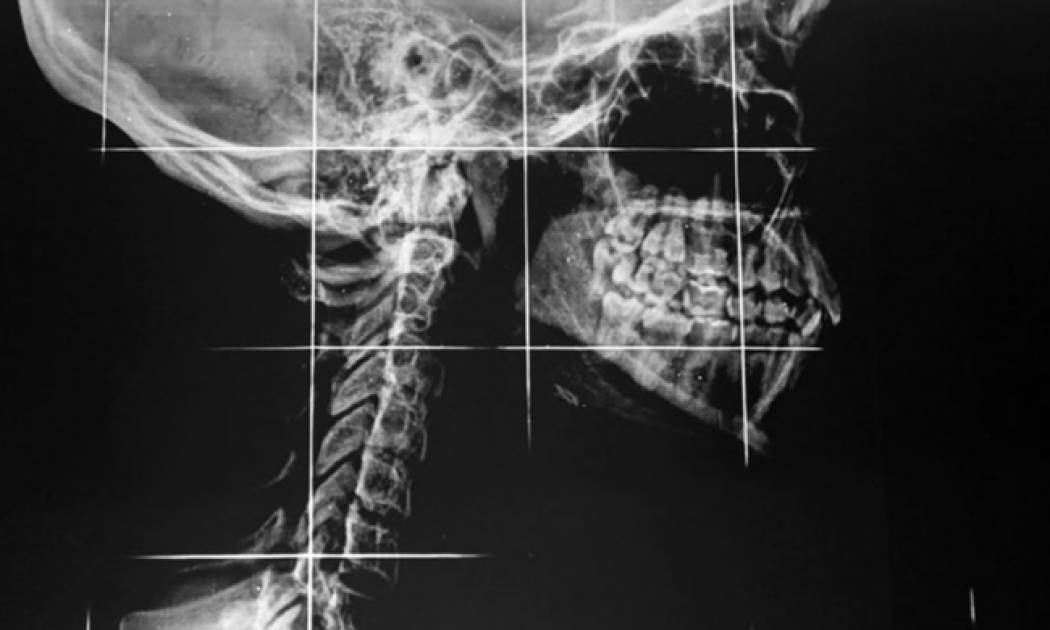

Εάν ξυπνήσετε το πρωί και νιώσετε ότι η γνάθος σας έχει «κλειδώσει» ή αισθάνεστε πόνο κάθε φορά που μασάτε ή χασμουριέστε, δείτε τι μπορεί να συμβαίνει και τι να κάνετε για να τον σταματήσετε.

Ο πόνος στη γνάθο μπορεί να προκληθεί από μια σειρά αιτίων, όπως πίεση στα ιγμόρεια, πρόβλημα της κροταφογναθικής άρθρωσης ή προβλήματα των δοντιών και των ούλων.